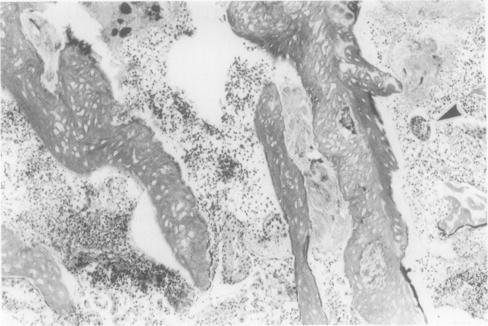

A case of autoimmune thyroiditis after long term treatment with lithium is described in a 29 year old Japanese woman with manic depression. Positive serum antithyroglobulin and antimicrosomal antibodies, diffuse goitre, and microscopic chronic thyroiditis, as well as the clinical history of long term lithium treatment were suggestive of lithium associated autoimmune thyroiditis. Microscopically, there was a mild degree of interstitial fibrosis and a moderate degree of lymphocytic infiltration. Some areas showed a moderate degree of stromal fibrosis and atrophic thyroid follicles. Lymphoid follicles with germinal centres, disrupted thyroid follicles with lymphocytic infiltration, and Hürthle cells were also observed. The differential diagnosis in patients presenting with these histological features includes painless (silent) thyroiditis, autoimmune thyroiditis and lithium associated autoimmune thyroiditis. A detailed clinical history is essential if the correct diagnosis is to be reached.

一名患有躁郁症的29岁日本女性,在长期接受锂治疗后出现了自身免疫性甲状腺炎。血清抗甲状腺球蛋白和抗微粒体抗体呈阳性、弥漫性甲状腺肿、显微镜下的慢性甲状腺炎以及长期锂治疗的临床病史提示为锂相关性自身免疫性甲状腺炎。显微镜下可见轻度间质纤维化和中度淋巴细胞浸润。部分区域显示中度间质纤维化和萎缩性甲状腺滤泡。还观察到有生发中心的淋巴滤泡、淋巴细胞浸润的破裂甲状腺滤泡以及许特莱细胞。具有这些组织学特征的患者的鉴别诊断包括无痛性(寂静性)甲状腺炎、自身免疫性甲状腺炎和锂相关性自身免疫性甲状腺炎。若要做出正确诊断,详细的临床病史至关重要。